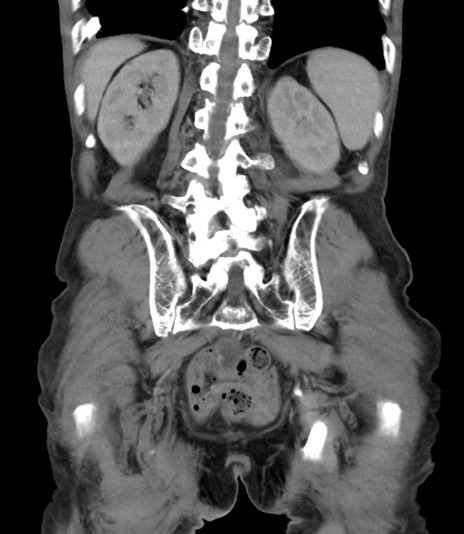

症例3(冠状断像)

【症例】 70歳代男性

【主訴】右鼠径部腫瘤、疼痛

【現病歴】本日朝より上記主訴あり、受診。

【既往歴】膀胱癌にて膀胱全摘、両側尿管皮膚瘻

【データ】WBC 5600、CRP 0.56